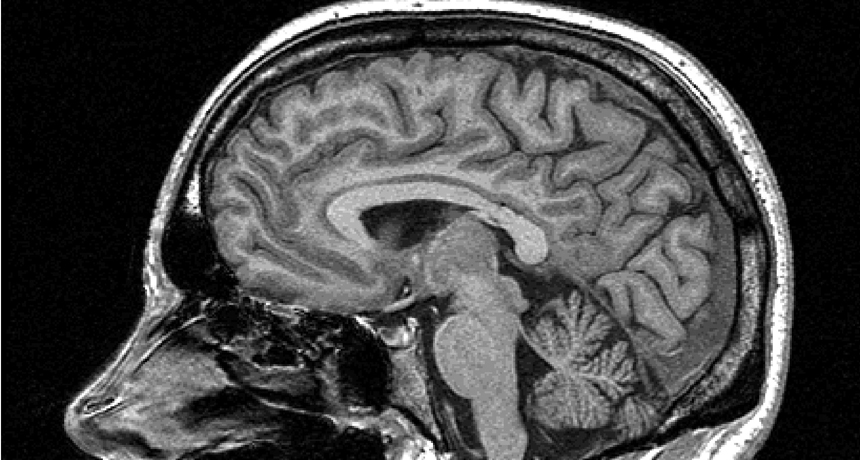

Brain scans showed that regions thought to be unique to humans share similarities with the brains of monkeys.

Courtesy of Oxford Centre for Functional MRI of the Brain